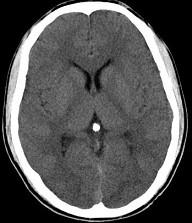

问题 男,23岁,近3天感到头痛、头晕,乏力,精神焦虑,CT检查如图所示,最可能的诊断为()

选项 A.脑萎缩 B.脑室出血 C.正常颅脑 D.脑水肿 E.胶质瘤

答案 C